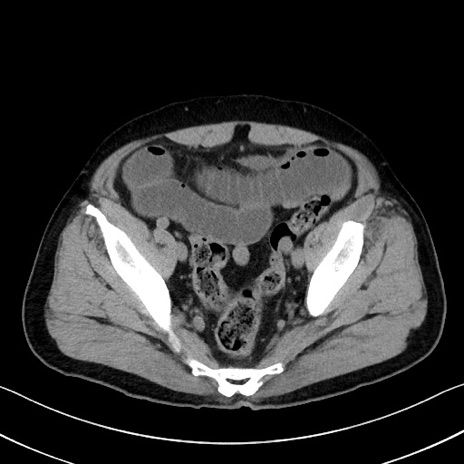

症例35(横断像)

【症例】70歳代 男性

【主訴】腹部膨満、嘔吐

【現病歴】昨日より腹部膨満感出現。本日増悪し、仙痛出現。嘔吐あり、受診。

【既往歴】糖尿病、胆摘後

【身体所見】BP 149/80mmHg、HR 74/min、BT 35.9℃、腹部:膨満、軟、圧痛なし。腸雑音減弱あり。上腹部正中切開瘢痕あり。

【データ】WBC 13500、CRP 1.72